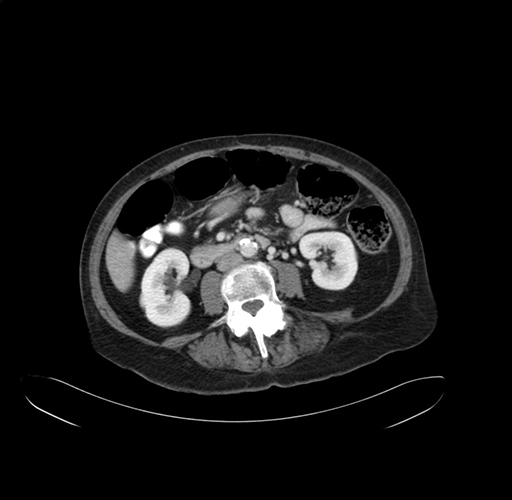

Pre-Chemo: Axial Venous

Axial Venous